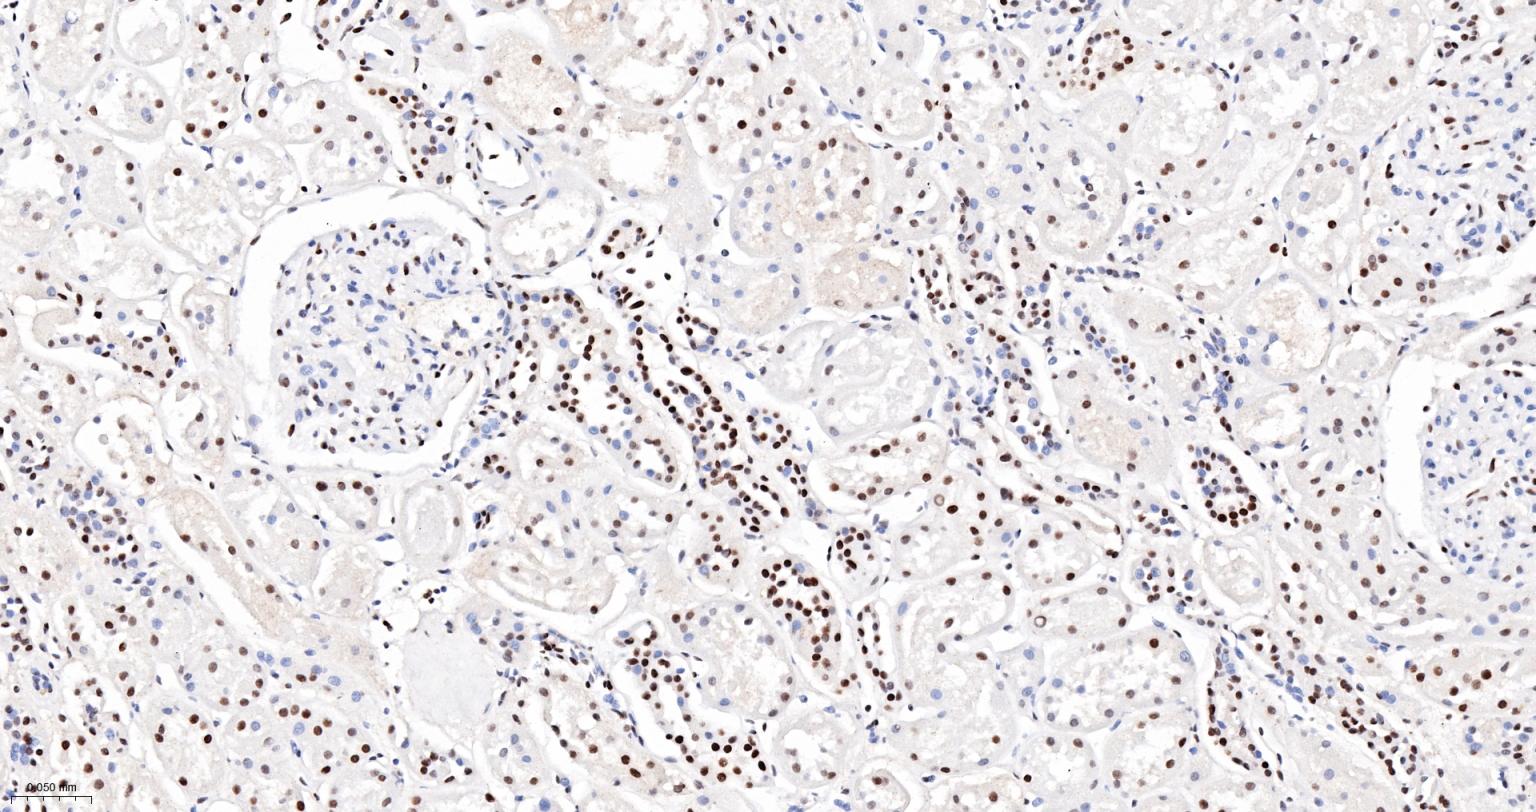

Paraformaldehyde-fixed, paraffin embedded Rat Kidney; Antigen retrieval by boiling in sodium citrate buffer (pH6.0) for 15 min; The section was incubated with ARID1A Monoclonal Antibody, Unconjugated (bsm-61359R) at 1:200 overnight at 4°C, followed by conjugation to the bs-0295G-HRP and DAB (C-0010) staining.